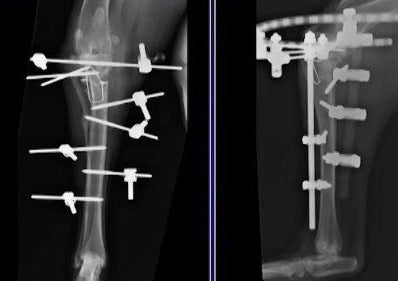

L'insuffisance de ligament cruciate crânienne est la cause la plus commune de chirurgie de nécessitant de claudication dans les chiens. L'instabilité résultante produit la maladie collective dégénérative et peut avoir pour résultat le trauma meniscal. La chirurgie est souvent recommandée pour s'améliorer le membre fonctionnent et il y a un certain nombre de procédures chirurgicales qui ont été décrites pour diriger des chiens avec cette condition. Cette séance se concentrera sur l'état actuel de direction chirurgicale de chiens avec l'insuffisance de ligament cruciate crânienne.